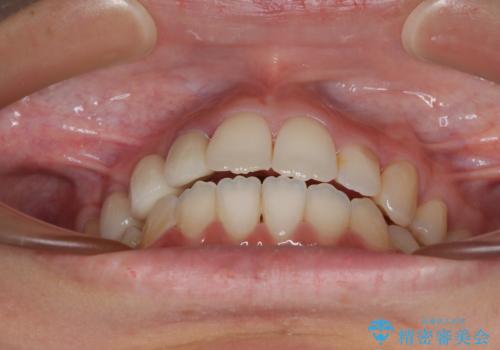

開咬と前突を改善 ワイヤー装置での抜歯矯正

結果として下顎の小臼歯は抜歯せず、右上の抜歯スペースはむし歯処置を兼ねてオールセラミックブリッジにて補綴治療を行うこととしました。

動かない歯での停滞や、出産と子育てなどにより治療期間は長期化しましたが、整った歯列にて仕上げることができました。